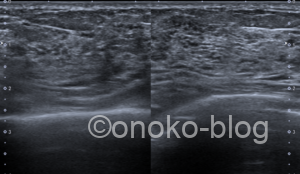

実際のエコー画像です。

※2枚目は乳頭下の画像です

『超音波画像では,皮下脂肪組織が減り,乳腺が厚みを増し,その内部の低エコー(豹紋パターン)がはっきりしてくる』

『クーパー靭帯を押し広げるようにして乳腺が増生している様子が観察される』

正常乳腺と比べてみると、

内部の低エコー像が明瞭ですね。

押し広げられたクーパー靭帯は今回確認できなかったのが残念です。